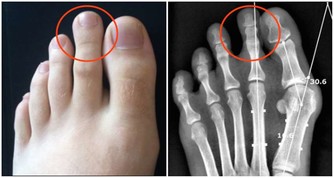

什麼樣的人是高凝體質?

答案是矮、粗、胖的人,特別是更年期的女同胞。

而且血型AB的人更容易高凝血稠。

還有脖子越短越容易高凝血稠。